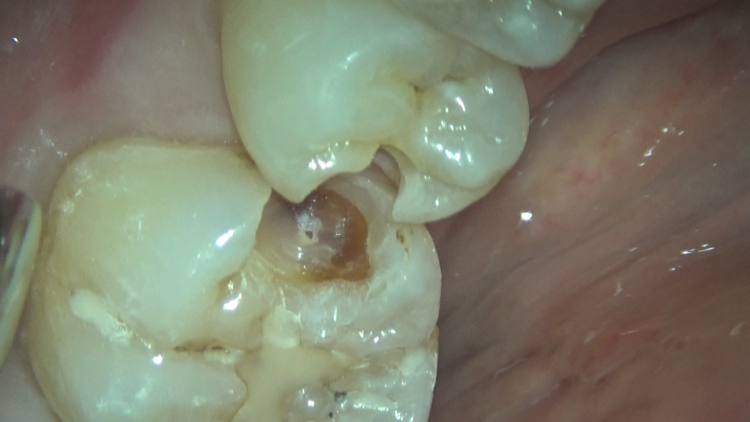

今回のケースは、詰め物の下に虫歯が残っていたため、患者さんのご希望もあり、セラミックでの治療を行いました。

マイクロスコープ下で虫歯の取り残しがないよう注意しながら除去し、歯の神経にも感染は認められなかったので、セラミックでの審美的な回復を行いました。